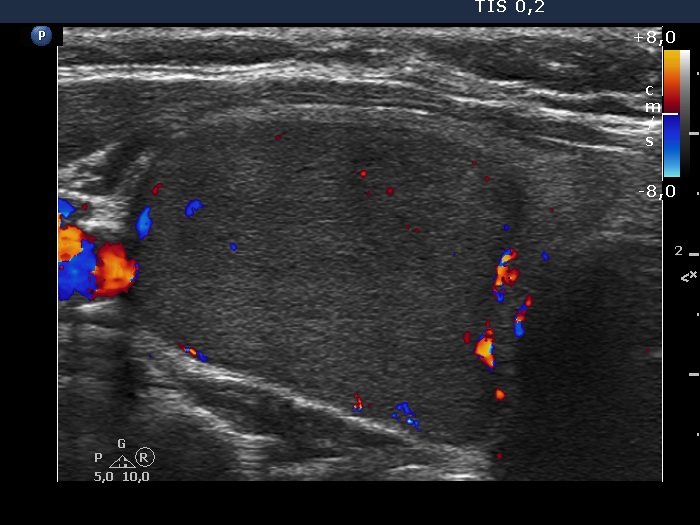

Right lobe, longitudinal scan

Right lobe, transverse scan, color Doppler mode. The nodule presents signs of perilesional blood flow.